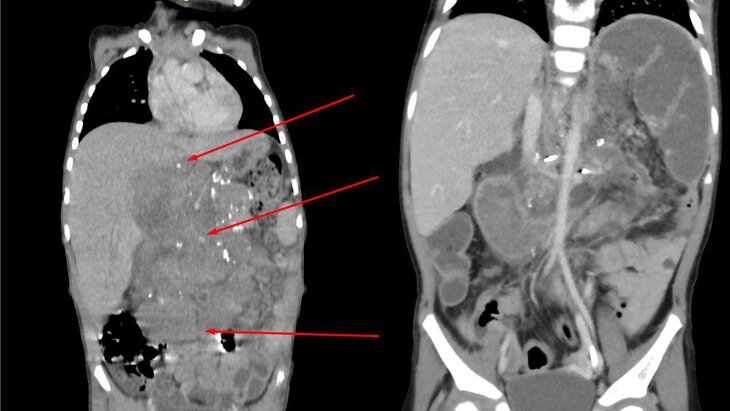

Фото: телеграм-канал "Российская детская клиническая больница"

Врачи Российской детской клинической больницы (РДКБ) спасли 3-летнюю девочку из Кабардино-Балкарии с огромной опухолью брюшной полости и метастазами. Об этом сообщила пресс-служба медучреждения.

В больнице рассказали, что изначально у ребенка резко выросла до 38 градусов температура, а также появилась тошнота и рвота. Кроме того, она чувствовала слабость и отказывалась от еды. В результате врачи в Кабардино-Балкарии выявили у девочки опухоль в области от диафрагмы до малого таза. Новообразование размером 12х13х15 сантиметров сдавливало желудок и кишечник.

В связи с этим для уточнения диагноза и комплексного лечения девочку направили в онкологическое отделение хирургических методов лечения РДКБ. Во время обследования у ребенка обнаружили нейробластому забрюшинного пространства в четвертой стадии с метастазами в костный мозг и лимфоузлы.

Ребенку сделали около шести курсов химиотерапии, чтобы медики собрали ее стволовые клетки для последующей пересадки. Уже после этого врачи приступили к 14-часовой операции по удалению новообразования. На данный момент хирургам удалось устранить свыше 95% от объема всей опухоли.

"Резекция оставшейся части образования несла огромные риски повреждения и потери органов", – уточнил завотделением РДКБ Иван Скапенков.

Он также рассказал, что опухоль находилась перед позвоночником и окружила аорту с другими жизненно важными сосудами брюшной полости. Именно поэтому, как утверждает Скапенков, операция проводилась с особой осторожностью.